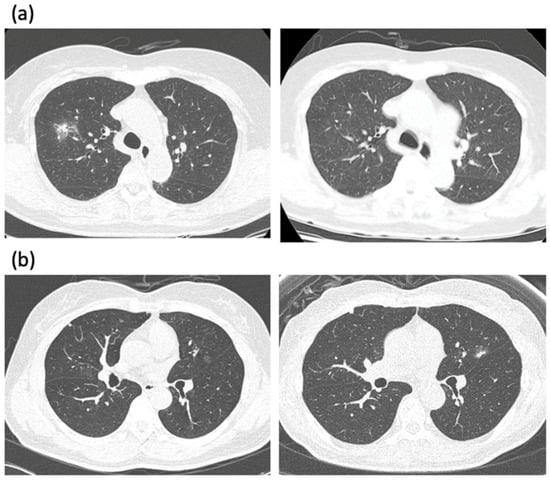

2. Predicting Malignant GGN

3. The First Dilemma: When to Intervene?